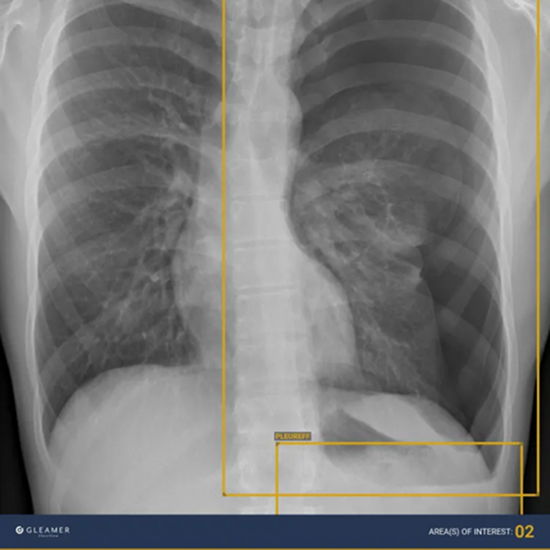

ChestView: Accelerated and Improved Detection of Thoracic Anomalies

With the help of ChestView, the detection of urgent findings such as pneumothorax, pleural effusion, and consolidation, as well as early cancer indicators like nodules and mediastinal masses can be accelerated and improved.

It was co-developed with AP-HP and is based on a robust database, which was partly cross-referenced with CT-scans.